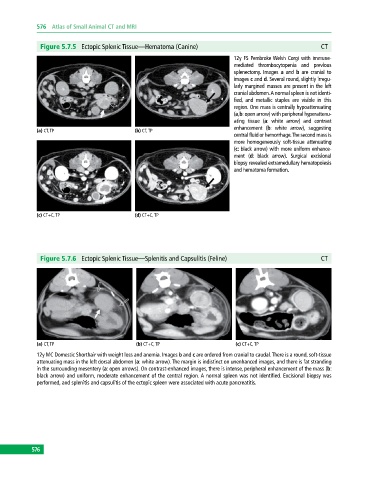

Figure 5.7.5 Ectopic Splenic Tissue—Hematoma (Canine) CT

12y FS Pembroke Welsh Corgi with immune‐

mediated thrombocytopenia and previous

splenectomy. Images a and b are cranial to

images c and d. Several round, slightly irregu

larly margined masses are present in the left

cranial abdomen. A normal spleen is not identi

fied, and metallic staples are visible in this

region. One mass is centrally hypoattenuating

(a,b: open arrow) with peripheral hyperattenu

ating tissue (a: white arrow) and contrast

enhancement (b: white arrow), suggesting

central fluid or hemorrhage. The second mass is

more homogeneously soft‐tissue attenuating

(c: black arrow) with more uniform enhance

ment (d: black arrow). Surgical excisional

biopsy revealed extramedullary hematopoiesis

and hematoma formation.

Figure 5.7.6 Ectopic Splenic Tissue—Splenitis and Capsulitis (Feline) CT

12y MC Domestic Shorthair with weight loss and anemia. Images b and c are ordered from cranial to caudal. There is a round, soft‐tissue

attenuating mass in the left dorsal abdomen (a: white arrow). The margin is indistinct on unenhanced images, and there is fat stranding

in the surrounding mesentery (a: open arrows). On contrast‐enhanced images, there is intense, peripheral enhancement of the mass (b:

black arrow) and uniform, moderate enhancement of the central region. A normal spleen was not identified. Excisional biopsy was

performed, and splenitis and capsulitis of the ectopic spleen were associated with acute pancreatitis.